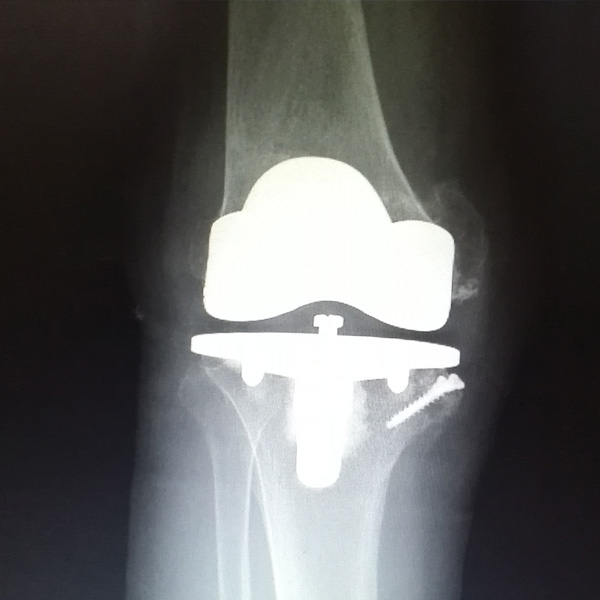

手術(shù)后手術(shù)前

膝關(guān)節(jié)內(nèi)翻

患者劉某某,女66歲,左側(cè)膝關(guān)節(jié)嚴(yán)重內(nèi)翻(俗稱的“羅圈腿”),疼痛到不能生活自理。經(jīng)平臺推薦到哈爾濱醫(yī)科大學(xué)附屬第二醫(yī)院骨關(guān)節(jié)科就診,......